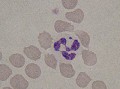

corps de Barr

Les corps de Barr sont de petites excroissances nucléaires physiologiques contenant un chromosome X inactivé. Ils se recontrent chez les femelles ou certains mâles qui présentent un mosaïcisme chromosomique XXY.